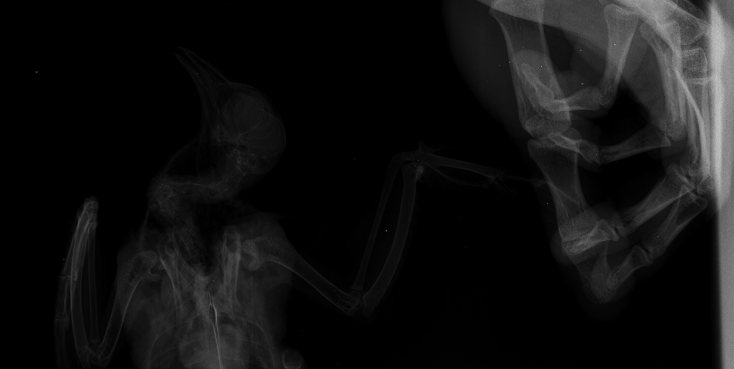

Duch Опубликовано 30 марта, 2020 #1 Опубликовано 30 марта, 2020 Здравствуйте! Приютился у нашего офиса, примерно 2 месяца назад, голубь и никак не улетал. Сделали вывод, что проблемы с крылом, т.к. левое он странно прижимал к себе. Положили в коробку, налили воды, насыпали гречи. Отогрелся спустя неделю, но крыло так и прижимал к себе. Предположили перелом крыла. Отвезли к орнитологу, сделали снимок (прикрепили к топику). Общий осмотр весьма позитивен, на снимке перелома нет. Выписали уколы витаминов и обезболивающих. Прокололи курс недели 2 назад - без изменений. На данный момент крыло так и прижимает к себе, огрызается, когда ему сыпят корм или доливают воды. Иногда клюёт и бьёт крылом, но только правым. Пока ждём выхода орнитолога из очередного отпуска, стараемся за ним ухаживать. В прошлую пятницу насыпали ему корм и подлили воды в плошку. Приехал в субботу вечером, дабы проведать. В итоге, он за целый день ничего не съел и не пил. На мои касания никак не реагировал: вжался в себя и стоял напуганный. Взял на руки, дабы осмотреть, как из под него показалась муха/слепень и тут же скрылась. Погуглил - оказывается, это - кровососки. Купил в ветеринарном отделе ампулу с препаратом, которую следовало разбавить 1,6л воды. Опрыскал её под крыльями, напоил водой из шприца и оставил так на день. Судя по корму, начал немного есть и пить. Кормплю гречкой, рисом и разваренным пшеном из шприца. Но сегодня обратил внимание, что он, когда клюёт сухой корм, как бы, промахивается и не может заглотить крупинку - гречка отскакивает в сторону и пытается еще раз захватить другую, но результат тот же. При всем при это, он четко видит мою руку и реагирует на неё соответствующим образом, т.е. слепоты нет Очень рассчитываю на вашу помощь! Ранее не имел опыта ухода за птицами

Виктория М. Опубликовано 30 марта, 2020 #2 Опубликовано 30 марта, 2020 (изменено) Здравствуйте. Нужен точный вес голубя. Помет желательно на листе белой бумаги. Проверьте нет ли наростов во рту , а также неприятныого запаха (кислого, тухлого). Кормить; 1 столовая ложка с горочкой 2 раза в день. Помимо гречи добавьте перловую крупу ,чечевицу или колотый горошек, пшеницу, овес без шелухи. Рис лучше уберите его можно но совсем немного. С каким препаратом ампула была? Все что обнаружил врач и все его назначения нужно выложить сюда на сайт, чтобы понимать чем вы лечили птицу. Какие витамины кололи какой курс и тд. Чтобы голубь начал нормально клевать зерно, в человеческой аптеке купите ноотропил таб или пирацетам . В вет аптеке нужно приобрести Фоспренил. Мух кровососок если вдруг еще обнаружите хорошо в тазике с водой вылавливать. Сажаете птицу в тазик с теплой водой, чтобы только голова на поверхности была, придерживаете аккуратно и так мин 10 -15 сидите с ним они начнут всплывать. Ваша задача не дать им вылететь из воды - передавить. Какое крыло он прижимает если смотреть на ренген? Изменено 30 марта, 2020 пользователем Виктория М.

маленький принц Опубликовано 1 апреля, 2020 #5 Опубликовано 1 апреля, 2020 (изменено) а можно рентген более крупный а не мелкий? у Вас на этой мелкой картинке трудно разглядеть подробности ВНОВЬ ЛЕТАТЬ и Здоровья Вашему голубю! чтобы узнавать новые ответы в Вашей теме нажмите пожалуйста наверху Вашей темы "подписаться" Изменено 1 апреля, 2020 пользователем маленький принц

Duch Опубликовано 1 апреля, 2020 Автор #6 Опубликовано 1 апреля, 2020 31.03.2020 в 01:36, Виктория М. сказал: Здравствуйте. Нужен точный вес голубя. Помет желательно на листе белой бумаги. Проверьте нет ли наростов во рту , а также неприятныого запаха (кислого, тухлого). Кормить; 1 столовая ложка с горочкой 2 раза в день. Помимо гречи добавьте перловую крупу ,чечевицу или колотый горошек, пшеницу, овес без шелухи. Рис лучше уберите его можно но совсем немного. С каким препаратом ампула была? Все что обнаружил врач и все его назначения нужно выложить сюда на сайт, чтобы понимать чем вы лечили птицу. Какие витамины кололи какой курс и тд. Чтобы голубь начал нормально клевать зерно, в человеческой аптеке купите ноотропил таб или пирацетам . В вет аптеке нужно приобрести Фоспренил. Мух кровососок если вдруг еще обнаружите хорошо в тазике с водой вылавливать. Сажаете птицу в тазик с теплой водой, чтобы только голова на поверхности была, придерживаете аккуратно и так мин 10 -15 сидите с ним они начнут всплывать. Ваша задача не дать им вылететь из воды - передавить. Какое крыло он прижимает если смотреть на ренген? Прикрепил назначение врача Во рту ничего подозрительного, как и в запахе. Может прозвучать неоднозначно, но он в вцелом, приятно пахнет) Ампула, которую разбавил в воде и опрыскивал 2 дня голубя под перья ( на тело) - "Дельцид" В воду окунали, правда держали минут 5. Ничего не всплыло и мы аккуратно его сушили феном, т.к. он сильно замёрз. Потом на форуме прочел, что насильное купание голубей недопустимо Глядя на рентген то, что раскрыто, т.е. правое. Делали снимок лёжа на спине, соответственно, по факту, это левое крыло

OFA Опубликовано 2 апреля, 2020 #25 Опубликовано 2 апреля, 2020 @Duch сама доктор смотрела рентген птицы? Что-то сказала? Нужно позвать нашего форумского доктора @Zosia посмотреть рентген. Может так разложена птица, но мне что-то кажется, что плечевой сустав не в порядке, но лучше пусть Зося посмотрит. Птица взрослая, клевать умеет, значит проблема или с жкт, или вертячка в такой форме.

маленький принц Опубликовано 2 апреля, 2020 #26 Опубликовано 2 апреля, 2020 @OFA рентген - в виде мелкой картинки просил автора залить рентген покрупнее

маленький принц Опубликовано 2 апреля, 2020 #30 Опубликовано 2 апреля, 2020 (изменено) @Duch вот рентген Вашего пациента Изменено 2 апреля, 2020 пользователем маленький принц

маленький принц Опубликовано 3 апреля, 2020 #33 Опубликовано 3 апреля, 2020 12 часов назад, Duch сказал: ну да, разве не его я прикрепил в прошлом сообщении? оно почему-то ужалось до мелких размеров если пойти по ссылке https://www.mybirds.ru/forums/uploads/monthly_2020_03/1SXcxYu_0rk.jpg.d7c82758490ddb04a65127b887286e57.jpg.28c0e1b9697a84b0cce71b1ee39e8254.jpg и открыть то видно что оно очень мелкое потому я скачав Ваш архив перезалил фото и увидев что оно ограничено по размерам дважды обрезав перезалил ещё раз